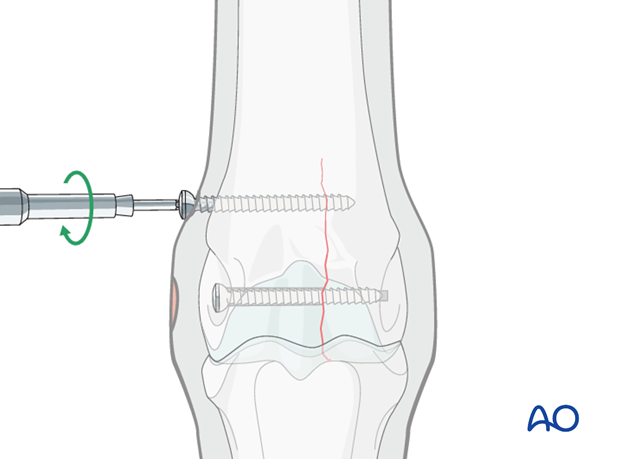

A second screw is placed approximately 2 cm proximal to the first screw.

For this and all other additional screws a countersink depression is prepared for seating the screw head. Countersinking should only be deep enough to prevent screw bending. The goal is NOT to bury the screw head. That will make it more difficult to remove the screw and potentially weaken the bone.

It may be helpful to leave the power screw driver attachment in the head of the first screw to assist alignment of the second screw.

Additional screws may be added according to the radiographically visible length of the fracture. In standing horses, however, most surgeons place only 2-3 screws.